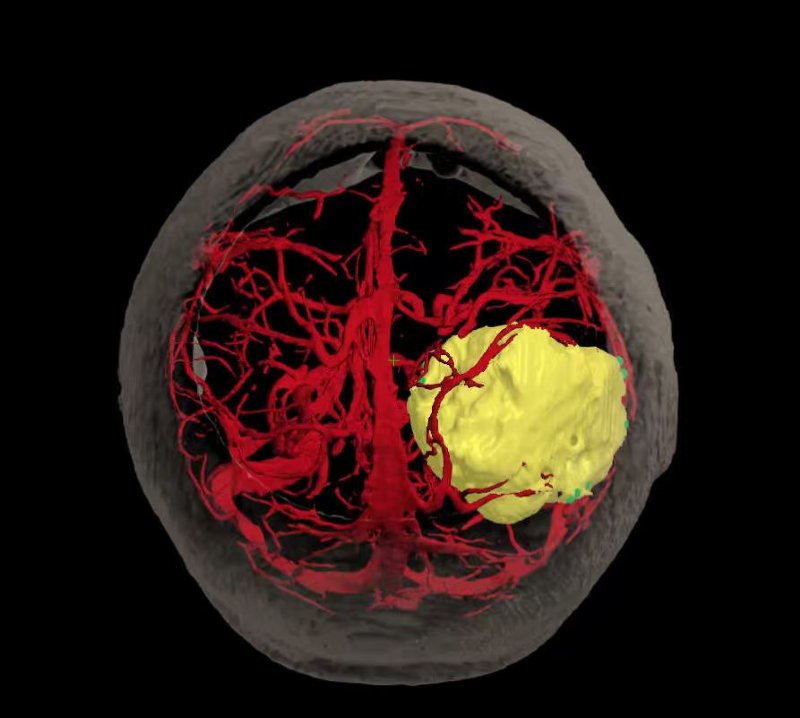

术前精准建模:运用3D Slicer软件整合多模态影像数据重建三维模型,清晰呈现肿瘤与周边功能区、血管的空间关系,为手术规划提供精准数字化依据。